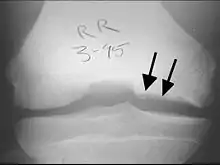

X-rays show lucency of the ossification front in juveniles. In older people, the lesion typically appears as an area of osteosclerotic bone with a radiolucent line between the osteochondral defect and the epiphysis. The visibility of the lesion depends on its location and on the amount of knee flexion used. Harding described the lateral X-ray as a method to identify the site of an OCD lesion.[36]

Magnetic resonance imaging (MRI) is useful for staging OCD lesions, evaluating the integrity of the joint surface, and distinguishing normal variants of bone formation from OCD by showing bone and cartilage edema in the area of the irregularity. MRI provides information regarding features of the articular cartilage and bone under the cartilage, including edema, fractures, fluid interfaces, articular surface integrity, and fragment displacement.[37][38] A low T1 and high T2 signal at the fragment interface is seen in active lesions. This indicates an unstable lesion or recent microfractures.[30] While MRI and arthroscopy have a close correlation, X-ray films tend to be less inductive of similar MRI results.[38]

Sagittal MRI: Linear low T1 signal at the articular surfaces of the lateral aspects of the medial condyle of the femur confirms the presence of OCD.